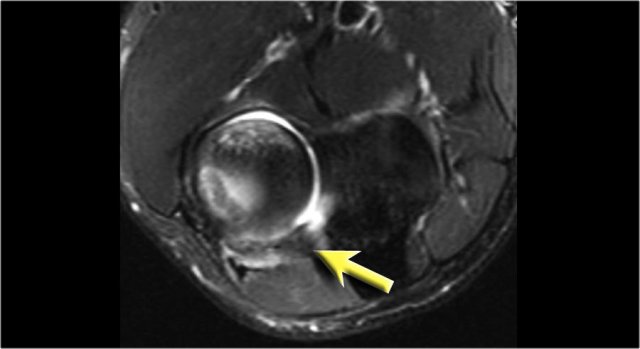

The radiograph is of a 15 year old baseball player with 4 year history of elbow pain and a recent episode of locking.

There is a focal lucency in the capitellum and some fragmntation.

This is typical for a osteochondral lesion of the capitellum and the locking is probably the result of loose bodies.

Continue with the MR...

The MR-arthrogram confirms the osteochondral lesion.

There is gadolinium in between the humerus and the osteochondral lesion which indicates that it is unstable.

If you don't have gadolinium, look for joint fluid undercutting the fragment.

There is a loose body in the posterior recess of the radiocapittelar joint.

Notice also the fragmentation as seen on the axial image.

The osteochondral lesion of the capitellum is typically seen in throwers and gymnasts (11-15 yrs), who get a lot of wrist and elbow problems due to weight bearing.